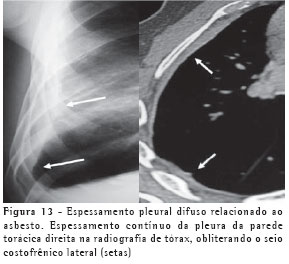

Espessamento pleural difusoO espessamento pleural difuso resulta de espessamento e fibrose da pleura visceral, com posterior fusão com a pleura parietal. Na radiografia é definido como espessamento contínuo da pleura parietal, estendendo-se por no mínimo um quarto da parede torácica, geralmente com obliteração do seio costofrênico. O espessamento pleural difuso é diagnosticado na TC quando o espessamento pleural se estende por no mínimo 8 cm no sentido longitudinal, 5 cm na largura e 3 mm na espessura (Figura 13).(12)